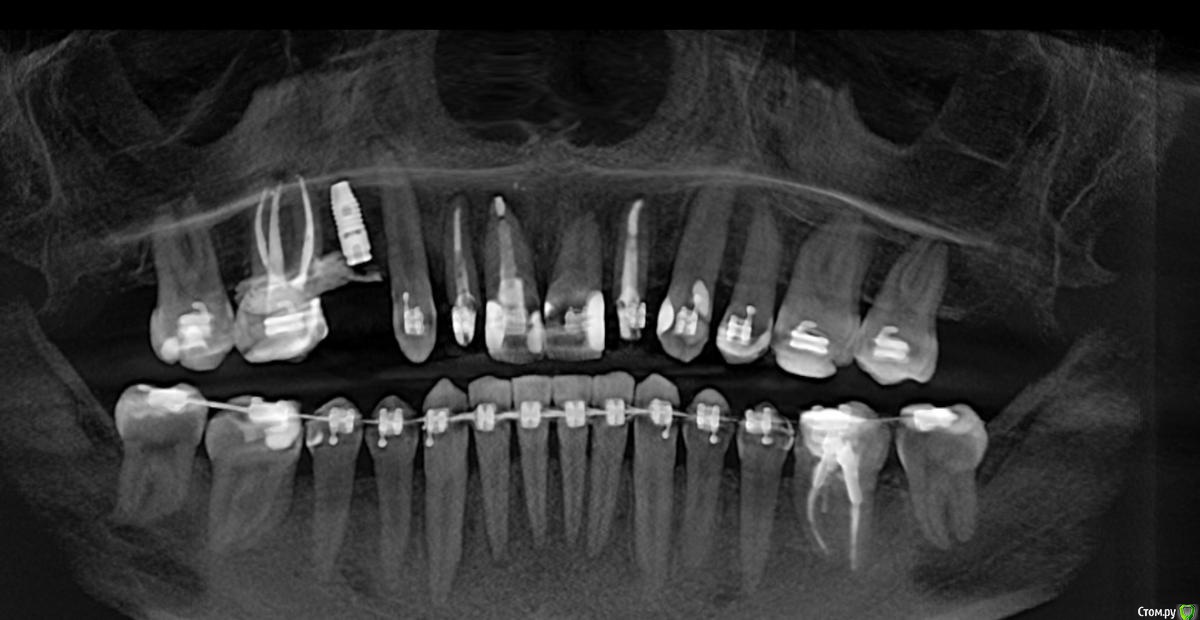

Al..ks Опубликовано 2 июня, 2019 Поделиться Опубликовано 2 июня, 2019 Прошла 30 мая имплантация 14 (3,5*9 Astra + заглушка - торк слабый. Изначально планировался сразу формирователь, но этот вариант мне больше по душе) + подсаживали десну к 16 (снимки КТ чуть позже добавлю). Пил сумамед, немисил (гадость походу - кишки крутило с него), лоратадин - три дня. Сейчас только ванночки хлоргексидина (хотя хирургическая щетка лежит с 12тыс щетинками, но забыл когда ей пользоваться начинать) Была слегка припухлость - на сегодня начала спадать остался только желтый синяк (как его побыстрее свести?)Вопрос по десне я правильно понимаю, что в районе швов это фибриновый налет? А вокруг 16-17 это тоже самое или пора панику наводить? Спасибо за ответы Ссылка на комментарий

Al..ks Опубликовано 6 июня, 2019 Автор Поделиться Опубликовано 6 июня, 2019 Вот и снимок Ссылка на комментарий